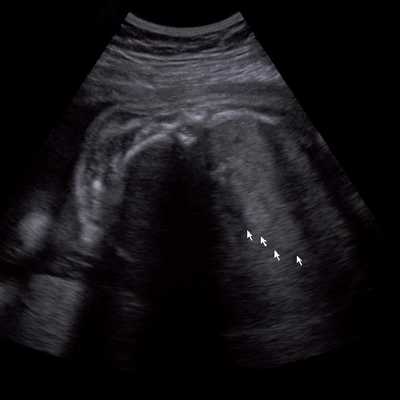

Под диафрагмой справа визуализировалось гиперэхогенное опухолевидное образование несколько неоднородной солидной структуры, с четкими ровными контурами, размером 50x38x35 мм. К нижнему полюсу данного образования прилежала правая почка, имеющая нормальные размеры, форму и структуру. Нижняя полая вена была смещена кпереди и влево. Обращала на себя внимание выраженная гепатомегалия, причем структура печени не была однородной. Она содержала множественные гиперэхогенные включения размерами до 17 мм, окруженные тонким гипоэхогенным периферическим ободком. Цветовое допплеровское картирование(ЦДК) демонстрировало интенсивную периферическую васкуляризацию опухоли (рис. 1-3).

Рис. 3. Метастазы в печени плода. Поперечное сечение брюшной полости плода. Гепатомегалия. В структуре печени плода определяются округлые включения несколько повышенной эхогенности (стрелки), с гипоэхогенным ободком - метастазы.

Был поставлен диагноз: беременность 31 нед 4 дня. Опухоль правого надпочечника плода с метастазами в печень. Рекомендовано динамическое ультразвуковое наблюдение за темпами роста новообразования и возникновением возможных осложнений.